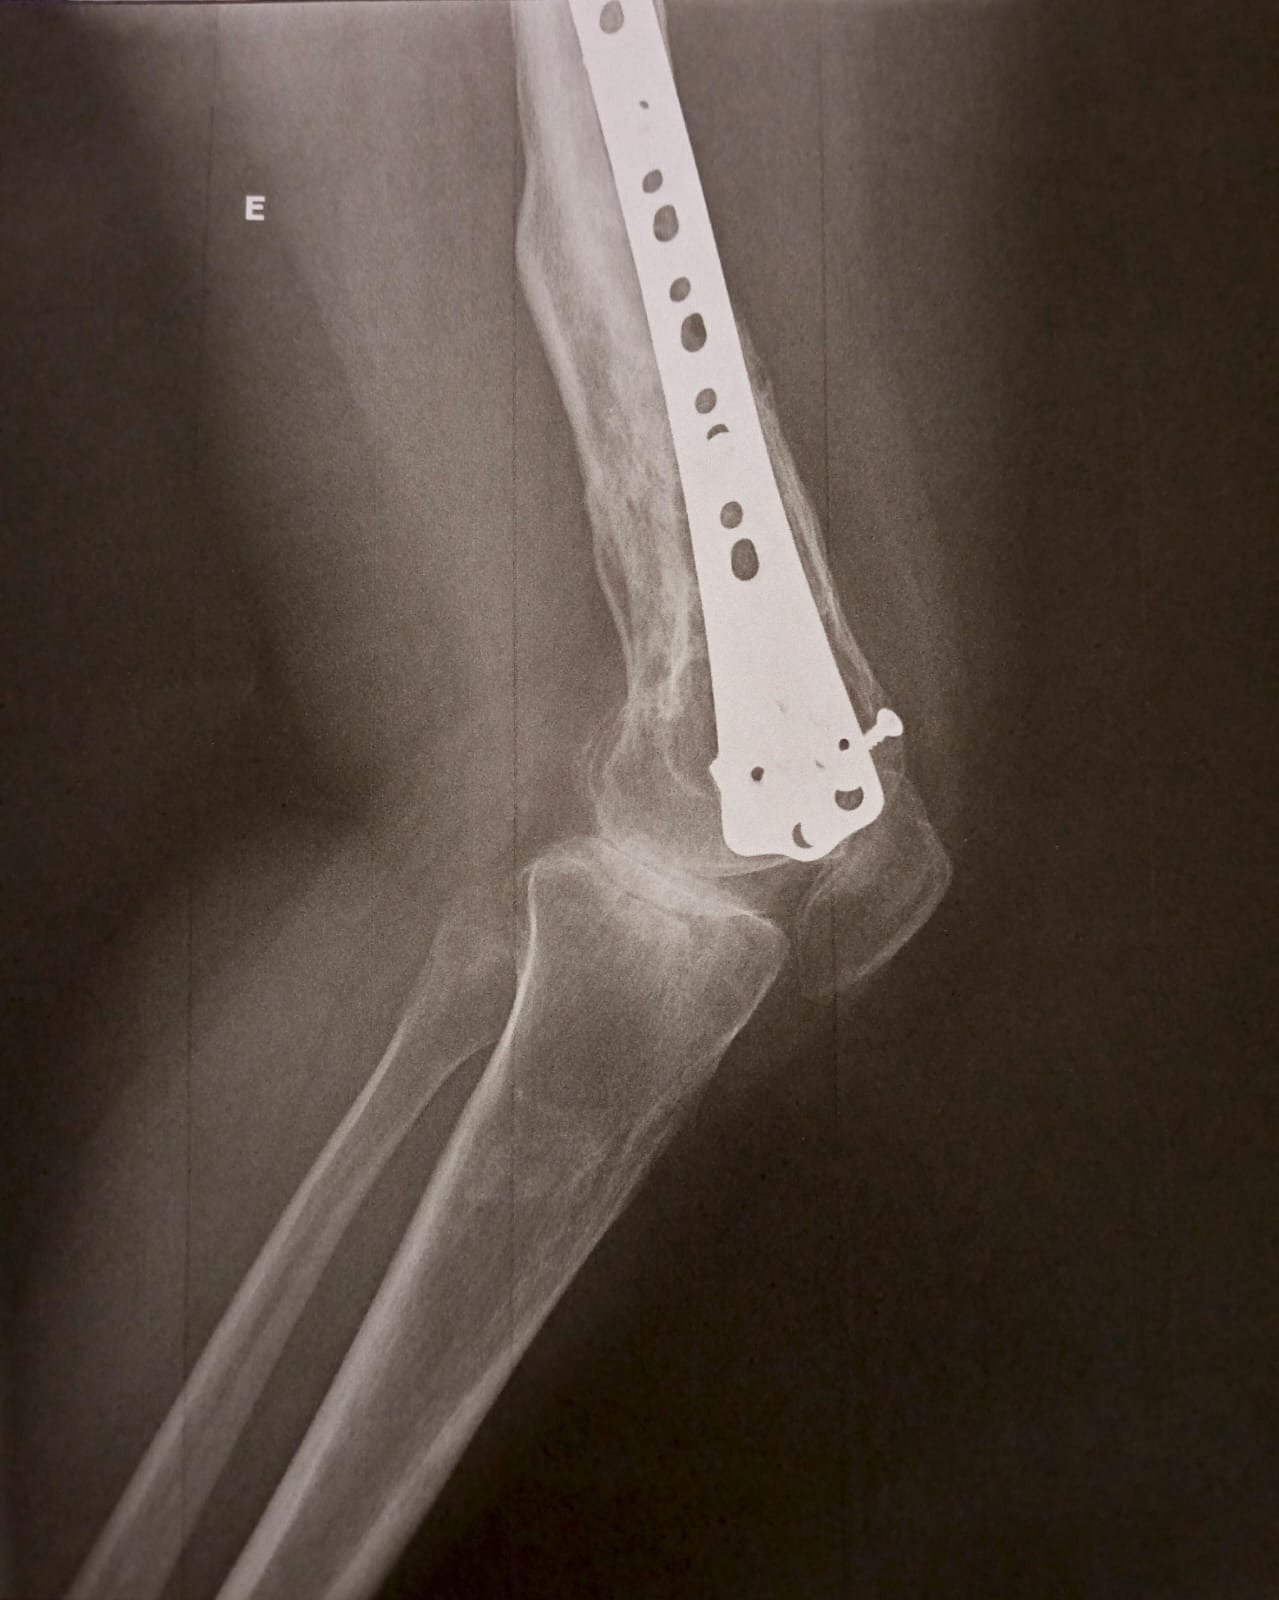

-Fracturas graves en su pierna

-Varias cirugías

Ella nunca se rindió. Siempre creyó que podía volver a caminar aunque no como antes pero sin dolor. Con el tiempo, las secuelas del accidente han pasado factura: hoy sufre artrosis avanzada, consecuencia directa de aquel choque. Los médicos han sido claros: necesita un trasplante de rodilla con urgencia.